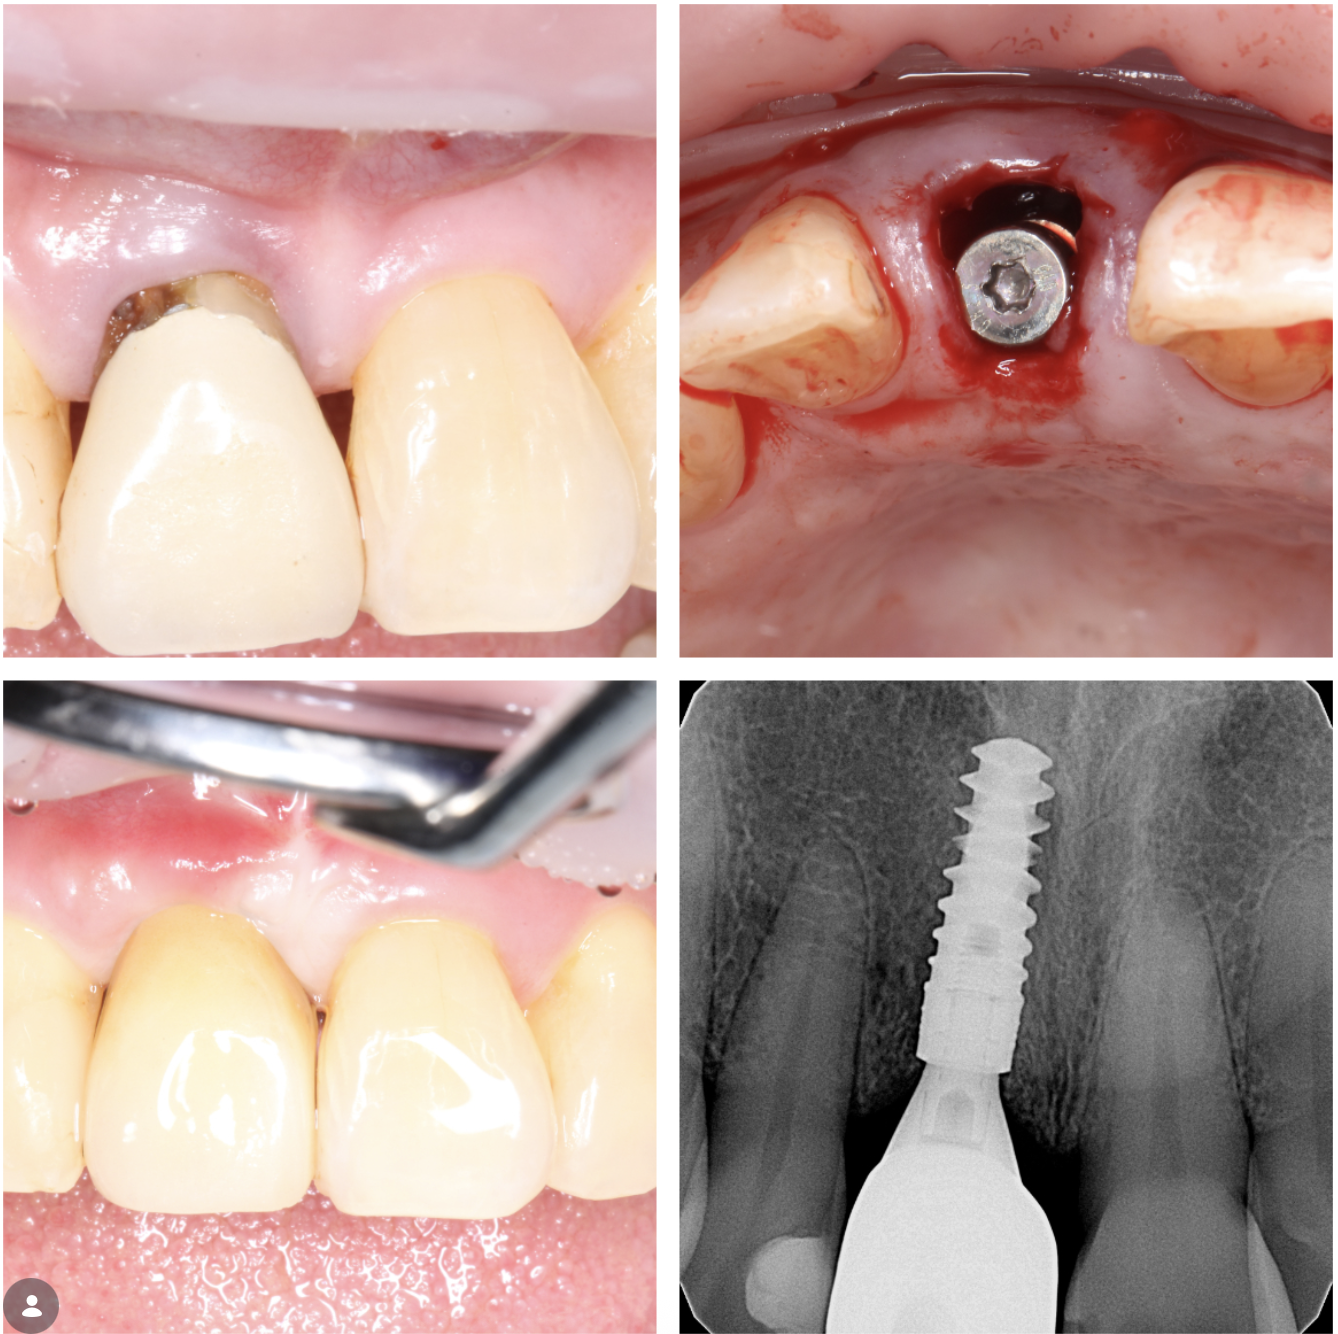

Before & Afters of Dental Implant Patients

Complete Dental Implant Cases Gallery

Surgical advances with SAME-DAY IMPLANTS in Vancouver BC

Using the most recent advances in dental implant technology, Dr. Noroozi is able to place single stage implants. These implants do not require a second procedure to uncover them but may require a minimum of six weeks of healing time before artificial teeth are placed. There are even situations where the implant can be placed at the same time as the tooth extraction and the artificial tooth can be inserted immediately following the implant placement – further minimizing your number of surgical procedures.

Dental implant treatment is sometimes a team effort between your periodontist and a restorative dentist.  Dr. Noroozi  at IMPrESS Perio Implant Center located in Burnaby BC performs the actual implant surgery, initial tooth extractions, and bone and gum grafting if necessary.  The restorative dentist (your dentist) or our specialists (if you do not have a dentist) will fit and make the permanent prosthesis. Your dentist or our specialists will also make any temporary prosthesis needed during the implant process.

General Disclaimer: The results in the photographs are examples only and do not imply any certainty of the result of a procedure, and all outcomes are subject to the circumstances of the individual patient.